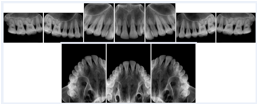

2. A patient requests cosmetic surgery to enhance their facial appearance. The case requires consultation between an orthodontist in New York and an oral surgeon in California. The cephalometric series of 2D projections constructed from the volumetric CT data that is used for the discussion is arranged by a Structured Display for transfer between the two practitioners.

Cephalometric Series Structured Display

Figure OO-2. Cephalometric Series Structured Display